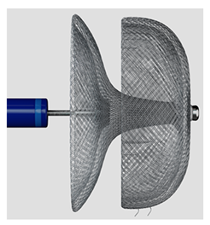

(Photo courtesy Biosense Webster) | Laminar LAAX System [93] Biosense Webster, Inc. | Rotational closure mechanism with integrated ball and lock design; self-expanding nitinol ball structure for LAA tissue engagement; no hooks or barbs required for anchoring, minimal LA-facing surface area; 18-F double-curve steerable guide system; two device sizes (12 mm and 16 mm). | Long-term durability data still being collected; currently in pivotal trial phase; learning curve for novel rotational closure technique; limited real-world experience outside clinical trials; optimal patient selection criteria still being established. |